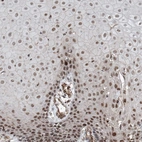

Immunohistochemical staining of human Placenta shows strong nuclear positivity in trophoblastic cells.